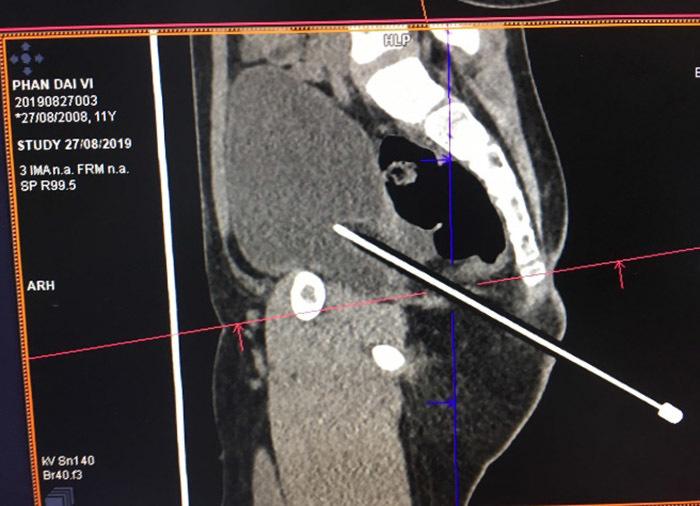

| Bút chì đâm vào hậu môn thấu bụng bé trai |

Ngay lập tức, bé trai này được sơ cứu, cho chụp CT – Scan bụng chậu và các xét nghiệm cần thiết.

Qua dựng hình trên phim, bé được chẩn đoán vết thương phức tạp vùng cạnh hậu môn – mông phải nghi ngờ thấu bụng và được chuyển mổ cấp cứu.

Khi nội soi vào ổ bụng, bác sĩ phát hiện một lổ thủng tại túi cùng Duoglas (ngách giữa trực tràng – bàng quang) kích thước khoảng 1x1,5 cm, độ sâu của bút chì đâm xuyên khoảng 15cm…